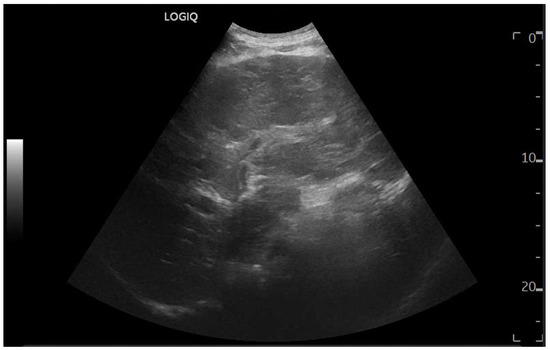

Abdominal ultrasound is a fundamental diagnostic tool in clinical practice, due to its availability, safety, and overall accuracy. This Special Issue will delve into the most recent technological and methodological innovations in abdominal ultrasound imaging, offering readers a comprehensive overview of advanced techniques, specific clinical indications, and solutions to emerging challenges. Among the various topics, it will cover the use of high-resolution probes, the integration of elastography for assessing liver fibrosis, and the application of contrast-enhanced ultrasound for identifying complex lesions. Strategies for training and professional development will also be examined to improve ultrasound performance and result interpretation.